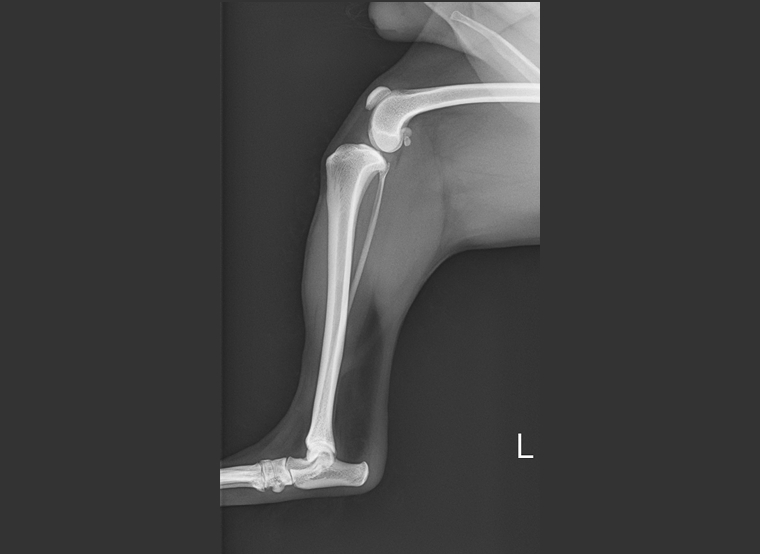

前十字靭帯は大腿骨と脛骨を結ぶ靱帯で、膝の安定性に関連します。この靱帯が損傷することで膝が不安定となり、患肢に体重をかけることができなくなります。原因として前十字靭帯の変性、加齢、外傷によるものがあります。症状は急性で顕著な跛行、痛み、おすわりの時にあしを投げ出すなどです。関節炎の進行や、半月板損傷の合併症が起こります。

治療は、保存療法としての内科治療と人工靭帯を使う関節外法、脛骨を切り大腿骨に対する角度を調整するTPLOなどの外科治療があります。